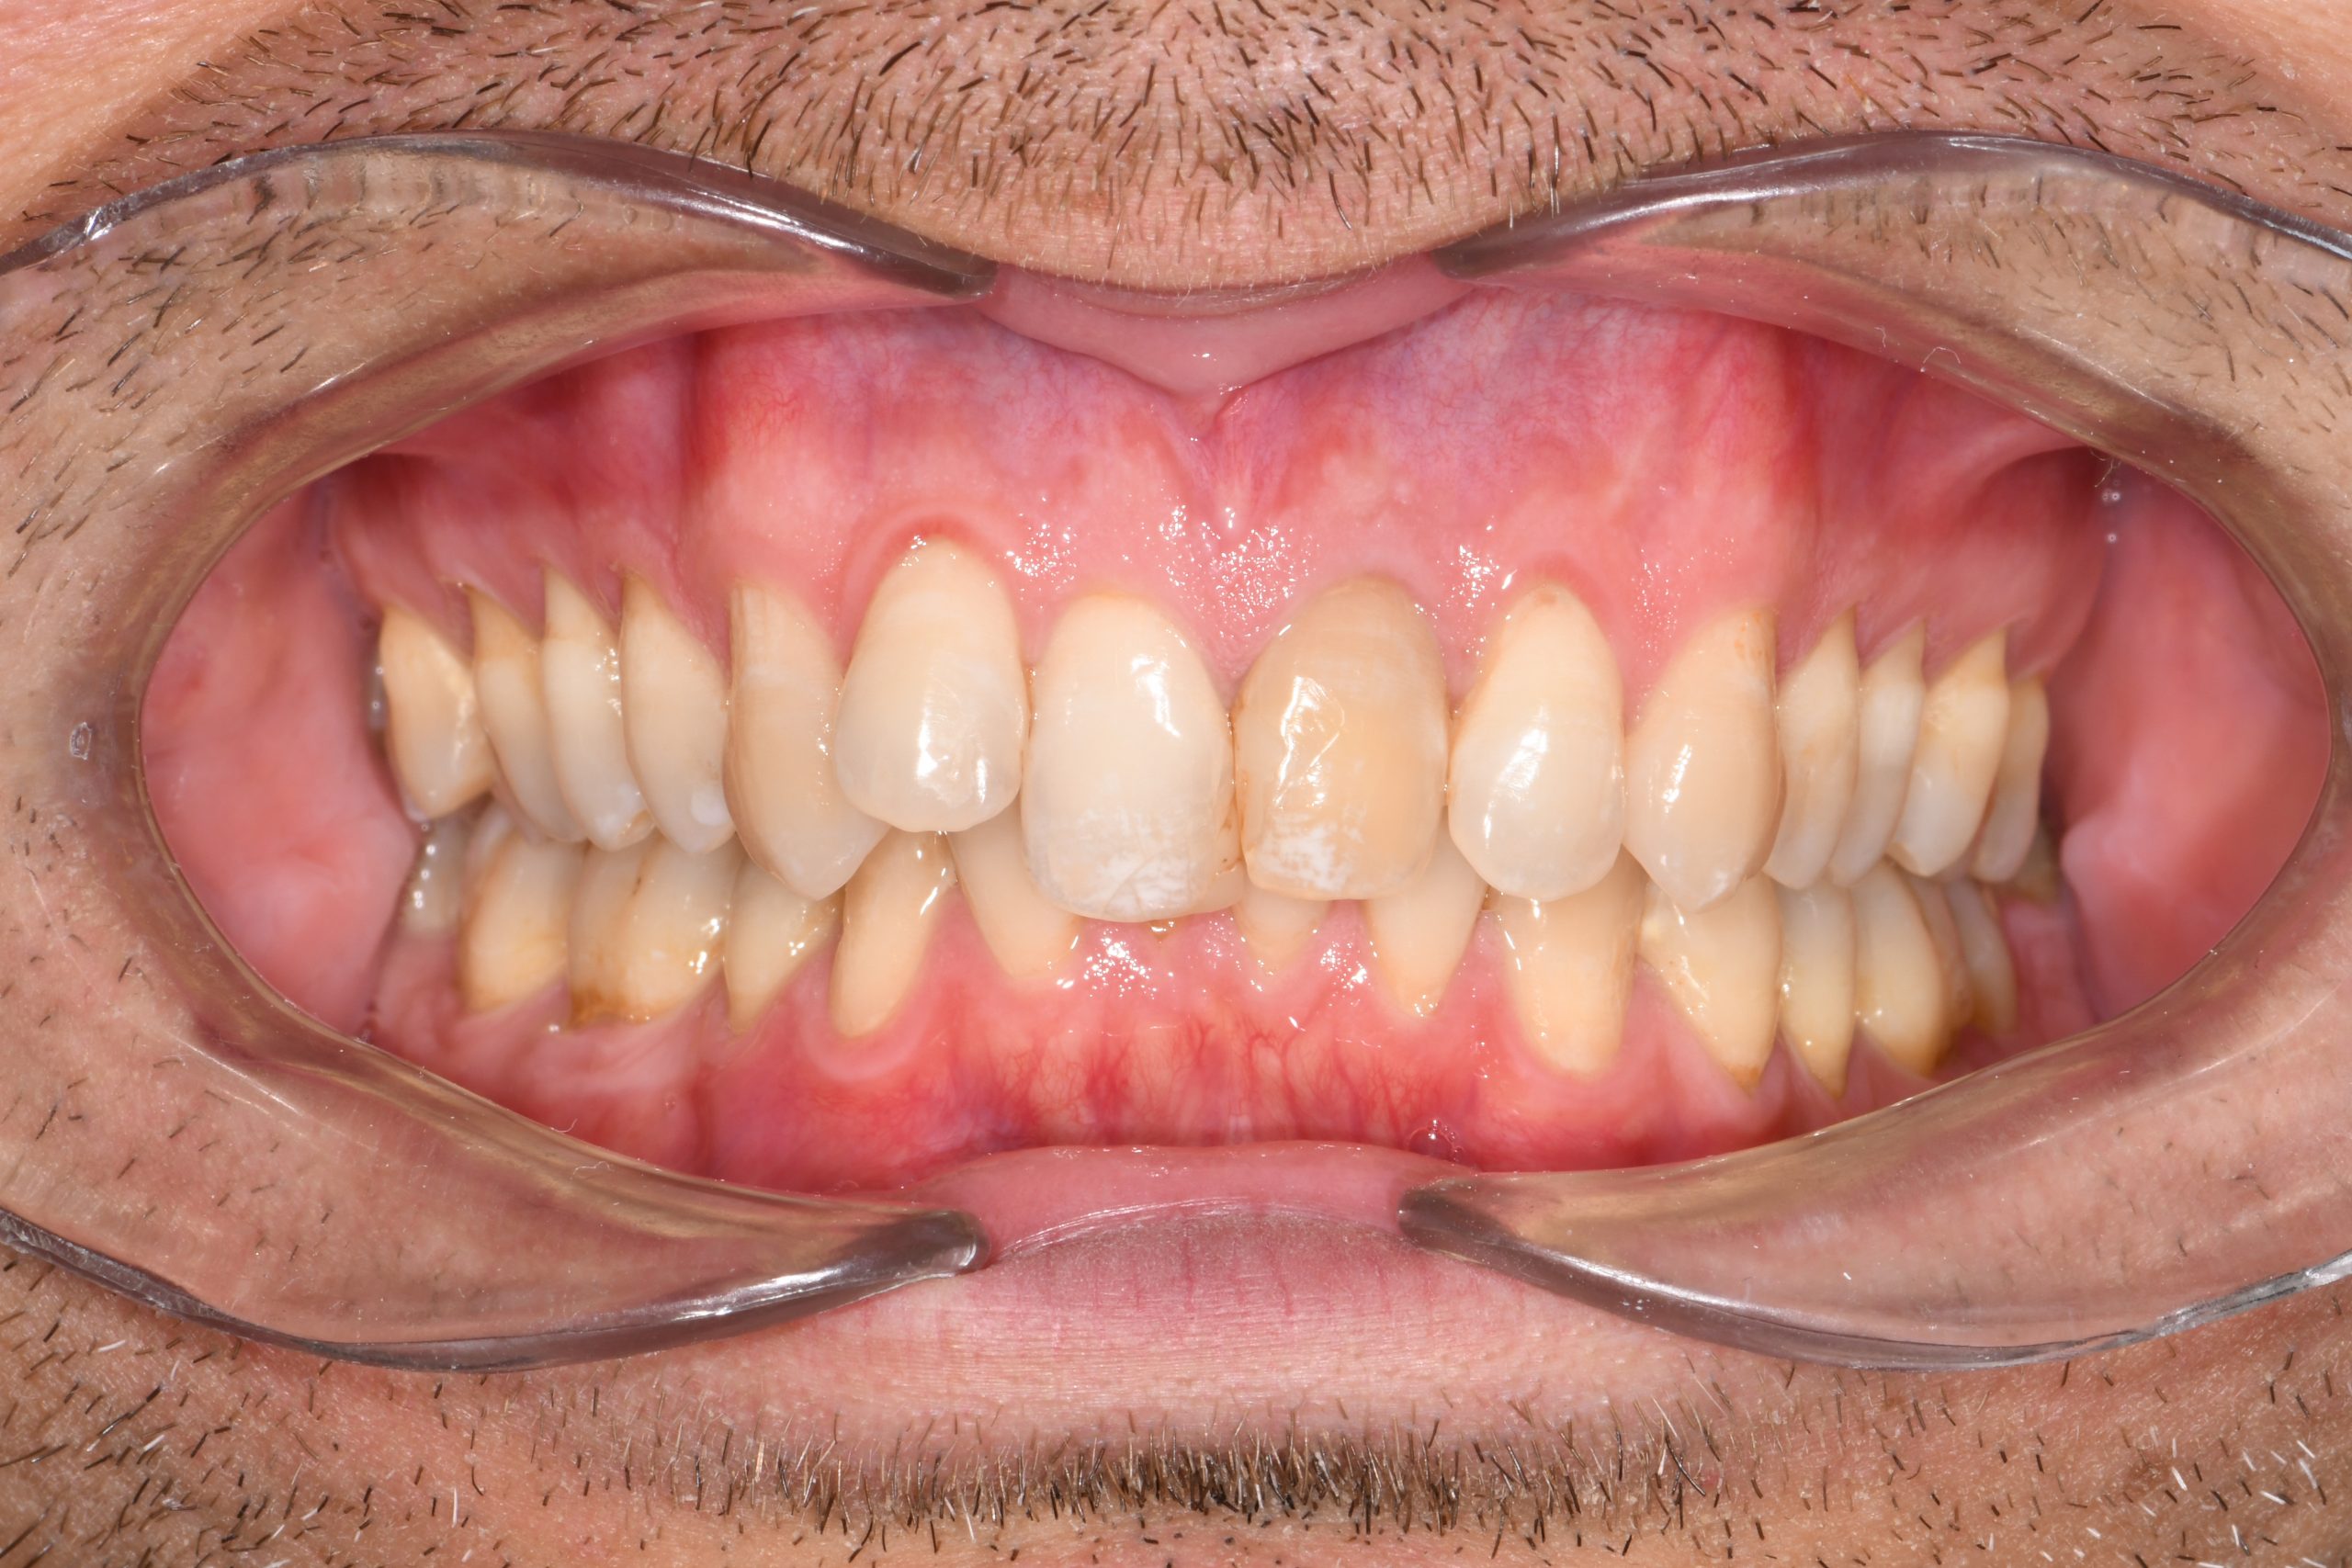

Az elmúlt évekből rengeteg szakmai referenciát tudnánk bemutatni, amelyek különböző fogszabályozási problémákat oldottak meg. Válogatva a több száz esetből, ezen az oldalon olyan képeket, információkat igyekeztünk bemutatni, amelyeknek a segítségével a jövőbeni pácienseinknek azt tudjuk üzenni: A Te fogsorod is lehet gyönyörű!

(Képeket a Pácienseink külön írásos beleegyezésével mutatjuk be!)